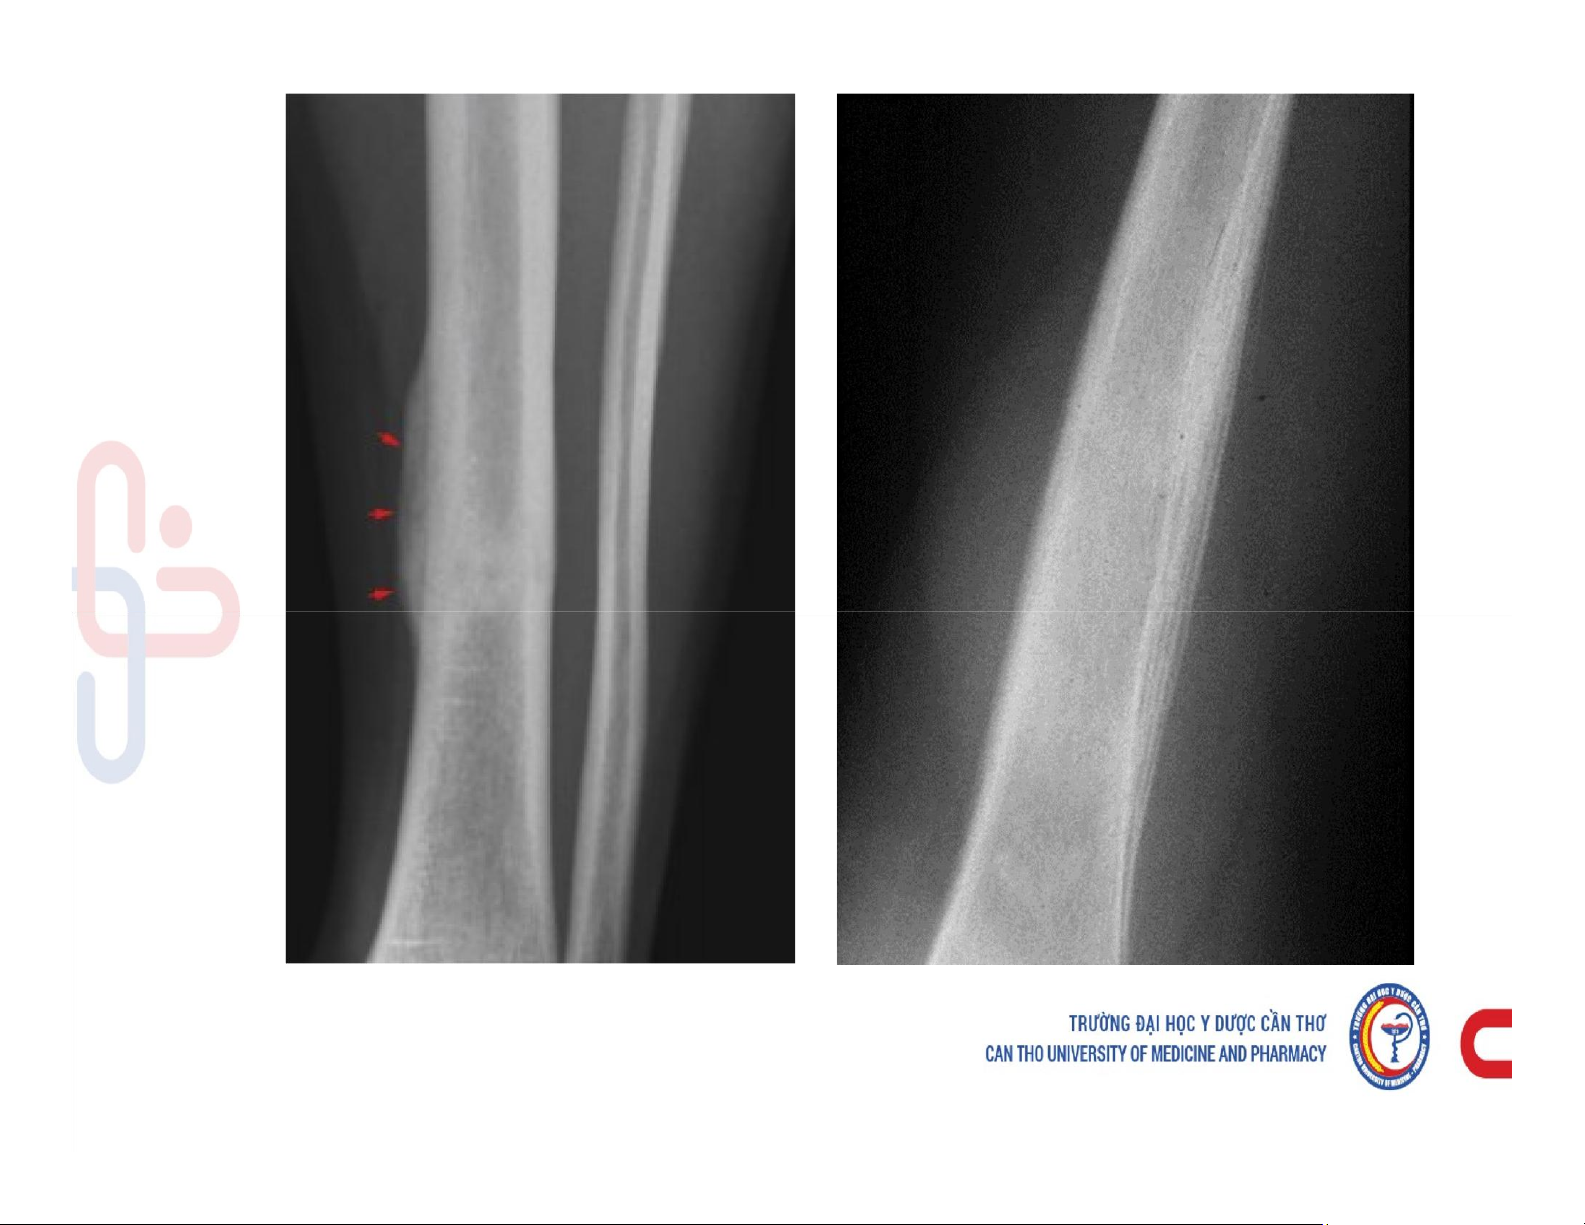

Mô tả và chú thích được các cấu trúc giải phẫu x quang xương khớp. Mô tả các dấu hiệu cơ bản trên phim x quang xương khớp. Phân tích được hình ảnh x quang bệnh lý của một số nhóm bệnh lý xương khớp. Các dấu hiệu cơ bản của phim. Tài liệu giúp bạn tham khảo, ôn tập và đạt kết quả cao. Mời đọc đón xem!